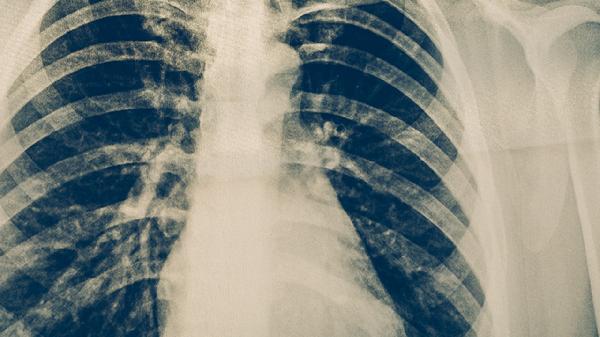

活动性肺结核患者咳嗽时产生的飞沫是主要传播途径。与患者密切接触时应保持1米以上距离,佩戴口罩并开窗通风。患者使用过的餐具需煮沸消毒,痰液要用含氯消毒剂处理。高危人群如医务人员需定期进行胸部影像学筛查。